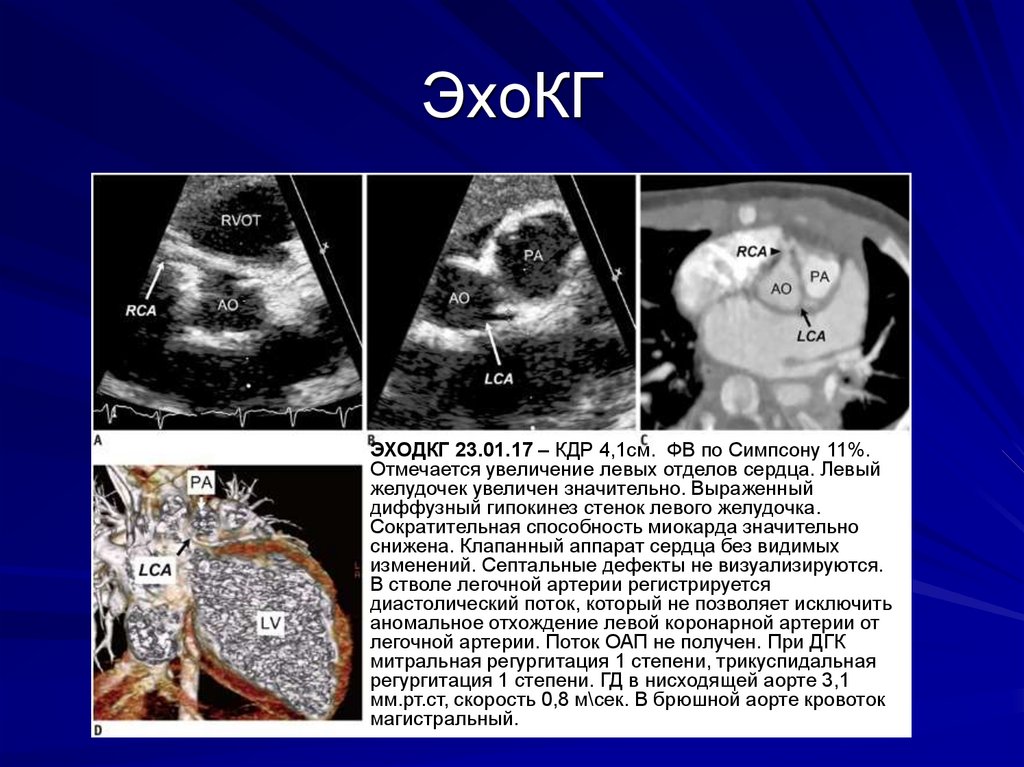

9. ЭхоКГ

ЭХОДКГ 23.01.17 – КДР 4,1см. ФВ по Симпсону 11%.

Отмечается увеличение левых отделов сердца. Левый

желудочек увеличен значительно. Выраженный

диффузный гипокинез стенок левого желудочка.

Сократительная способность миокарда значительно

снижена. Клапанный аппарат сердца без видимых

изменений. Септальные дефекты не визуализируются.

В стволе легочной артерии регистрируется

диастолический поток, который не позволяет исключить

аномальное отхождение левой коронарной артерии от

легочной артерии. Поток ОАП не получен. При ДГК

митральная регургитация 1 степени, трикуспидальная

регургитация 1 степени. ГД в нисходящей аорте 3,1

мм.рт.ст, скорость 0,8 м\сек. В брюшной аорте кровоток

магистральный.